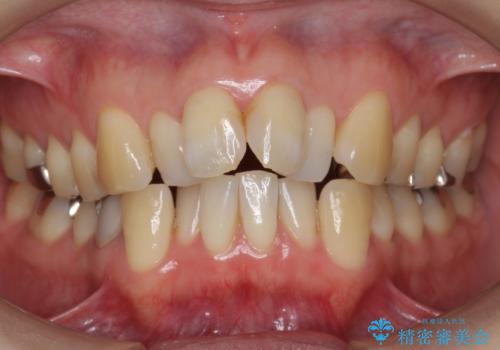

- 前歯の並びを主訴に来院。

前歯が出ており、また、左上の側切歯が1本生まれつき少ない状態でした。

また、右の奥歯の関係も上が前にある状態で大きくずれていました。

今回は左右とも1歯対2歯の関係であるため、それは変えずに前歯を可及的にひっこめて足りない部分をブリッジで補う治療としました。

奥歯の関係を完全に1級にするには右上の小臼歯の抜歯が必要でしたが、もともと左上の前歯が生まれつき少ないため今回は歯を抜かずに治療しています。